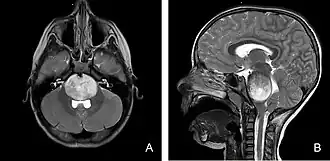

Der Tumor kann mittels Schnittbildgebung, vor allem der Magnetresonanztomographie, dargestellt werden. Der Tumor zeigt keine oder nur eine geringe Aufnahme von Gadolinium-Kontrastmittel.[5][8]